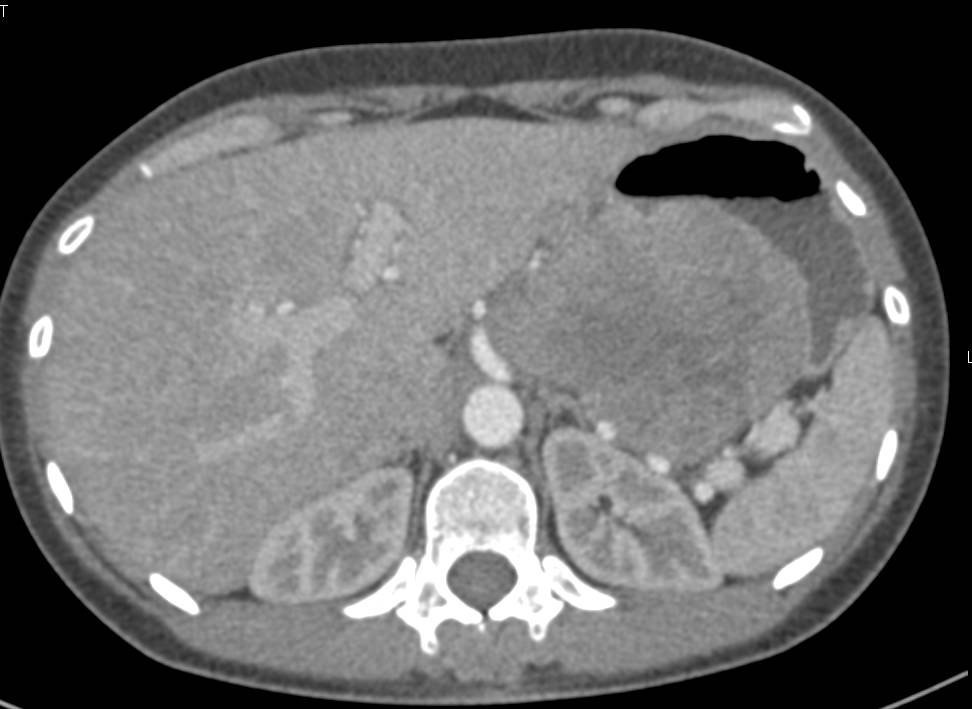

Antral Carcinoma with Carcinomatosis and Incidental Pulmonary Embolism